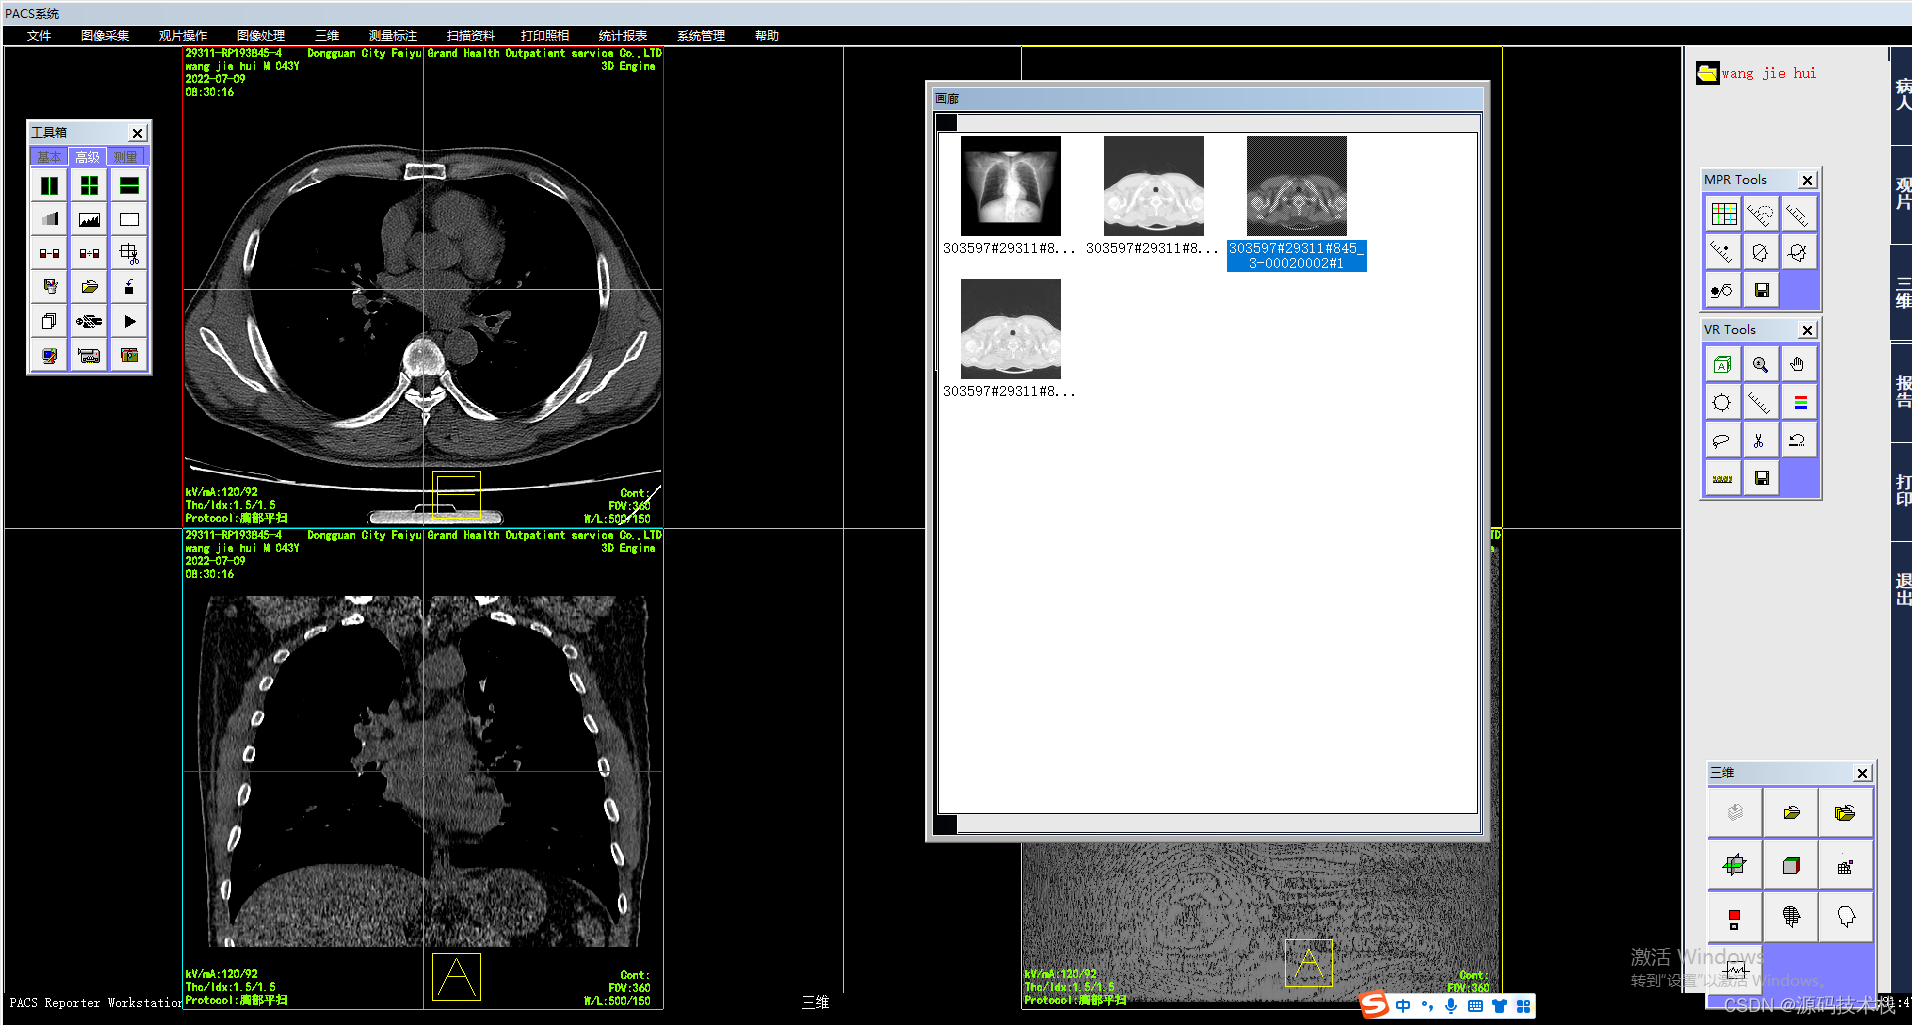

6、VRT

VRT(Volume Rendering Technology),这种三维成像功能非常强大,形态及色彩逼真,绝对是CT三维重建中的“高富帅”,可以对动静脉血管、软组织及骨结构等进行立体塑形成像,也可以显示支气管树、结肠及内耳等结构,对于复杂结构的成像有一定优势。

VRT图像直观生动,深受广大医生的喜爱,称得上是辅助诊断、显示病变的大杀器,但是我们要注意一点,VRT图像的伪彩设置很重要,不恰当的伪彩设置会将血管外层像素过滤掉,显示的血管狭窄的程度会比真实情况严重。